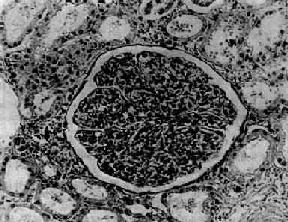

图12-7 弥漫性毛细血管内增生性肾小球肾炎 肾小球内细胞数量增多,系膜细胞和内皮细胞增生并有少量中性白细胞浸润,毛血管腔狭窄 上皮细胞一般无明显增生,少数严重的病例肾小球的壁层和脏层上皮细胞可增生,形成新月体。这种病变容易引起肾小球纤维化。如数量少,对功能影响不大。如病变广泛,可发展为新月体性肾炎。 在电子显微镜下可见肾小球系膜细胞和内皮细胞增生肿胀。基底膜和脏层上皮细胞间有致密物质沉积。这些沉积物大小不等,有的很大,在基底膜表面呈驼峰状或小丘状(图12-8,图12-9)。沉积物表面的上皮细胞足突多消失。基底膜变化不明显有时边缘稍不规则。沉积物一般在发病后几天就可出现,在4~6周内消失。有时基底膜内侧内皮细胞下和系膜内也可见小型沉积物。

图12-8 毛细血管内增生性肾小球肾炎 电镜下见肾小球毛细血管基底膜表面上皮细胞下有多数驼峰状电子致密沉积物

图12-9 毛细血管内增生性肾小球肾炎 电镜下见驼峰状沉积物位于毛细血管基底膜表面。沉积物表面有上皮细胞覆盖,上皮细胞足突消失 免疫荧光法检查显示,在肾小球毛细血管壁表面有免疫球蛋白和补体沉积(主要为IgG和C3),呈颗粒状荧光。系膜内也可有类似沉积物。 肾小球的病变可引起相应的肾小管缺血,肾小管上皮细胞常有浊肿、玻璃样变和脂肪变等。管腔内含有从肾小球滤过的蛋白、红细胞、白细胞和脱落上皮细胞。这些物质在肾小管内凝集,形成各种管型,如蛋白管型、透明管型、细胞管型(如红细胞、白细胞或上皮细胞管型)、颗粒管型。 肾间质内常有不同程度的充血、水肿和少量淋巴细胞、中性粒细胞浸润。 肉眼观,早期变化不明显。以后肾轻度或中度肿大、充血、包膜紧张、表面光滑、色较红,故称大红肾。若肾小球毛细血管破裂出血,肾表面及切面可见散在的小出血点如蚤咬状,称蚤咬肾。切面可见皮质由于炎性水肿而增宽,条纹模糊与髓质分界明显。 【临床病理联系】 这种肾炎的主要临床症状为尿的变化,水肿和高血压。 1.尿的变化由于肾小球毛细血管损伤,通透性增加,故常有血尿、蛋白尿、管型尿等。 (1)血尿:血尿常可反映肾小球毛细血管损伤的情况。轻度血尿需用显微镜才能发现。严重的血尿,肉眼可见尿呈鲜红色。有时尿中红细胞溶解,血红蛋白在酸性尿中转变成酸性血红素,使尿呈棕红色。 (2)蛋白尿:蛋白尿的程度不同,一般不很严重,但少数病人尿中可有大量蛋白质。 (3)管型尿:在肾小管内凝集形成的管型随尿液排出,尿液内可出现各种管型,称为管型尿。 (4)少尿:由于肾小球细胞增生肿胀,压迫毛细血管,致管腔狭小,肾血流受阻,肾小球滤过率降低,而肾小管再吸收无明显障碍,可引起少尿,致水钠在体内潴留。严重者并可有含氮代谢产物潴留,引起氮质血症。 2.水肿病人常有轻度或中度水肿,往往首先出现在级织疏松的部位如眼睑。水肿的原因主要是由于肾小球滤过减少,而肾小管再吸收功能相对正常,引起水钠潴留。此外,也可能与变态反应所引起的全身毛细血管痉挛和通透性增加有关。 3.高血压病人常有轻至中度高血压。过去认为这种肾炎时的高血压与肾小球毛细血管阻塞,肾组织缺血引起肾素分泌增加有关。但病人血中肾素浓度多在正常范围之内。因此高血压的主要原因可能与水钠潴留引起的血量增加有关。严重的高血压可导致心力衰竭及高血压性脑病。 【结局】 这种肾炎的预后与年龄和病因有一定关系。儿童链球菌感染后肾小球肾炎的预后很好,95%以上可在数周或数月内症状消失,病变消退,完全恢复。少数病人病变消退较慢,肾小球系膜增生,可持续数月甚至1~2年。临床上,病人常有迁延性蛋白尿和复发性血尿。有时无明显症状,成为隐匿性肾炎。这种病变大多以后仍可消退,恢复正常。少数病人(约占1%~2%)临床症状消失,但病变持续不退,以后症状可反复,逐渐发展为慢性硬化性肾小球肾炎。极少数病人病变严重,发展较快,同时有明显的肾球囊上皮细胞增生,形成大量新月体,可发展为新月体性肾小球肾炎。这些病人常迅速发生急性肾功能衰竭,预后差。还有极少数(<1%)病人病变严重,发展迅速,在短期内发生肾功能衰竭、心力衰竭或高血压性脑病。 一般成人患感染后肾小球肾炎者预后较差,发生肾功能衰竭和转变为慢性肾炎者较多。此外,由其他感染引起的肾炎转变为慢性肾小球肾炎者,比链球菌感染后肾炎转为慢性者多见,预后也较差。